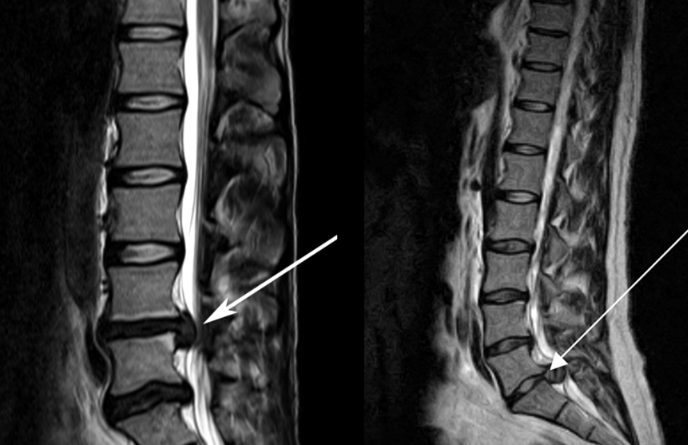

3、核磁共振(MRI):核磁共振沒(méi)有輻射,可以多方位成像(橫斷面、冠狀面、矢狀面和斜面),對(duì)解剖細(xì)節(jié)顯示較好,對(duì)組織結(jié)構(gòu)的細(xì)微病理變化更敏感(如骨髓的浸潤(rùn)),可以排除神經(jīng)和脊柱腫瘤等。對(duì)于一些落到椎管的髓核組織也不會(huì)遺漏。